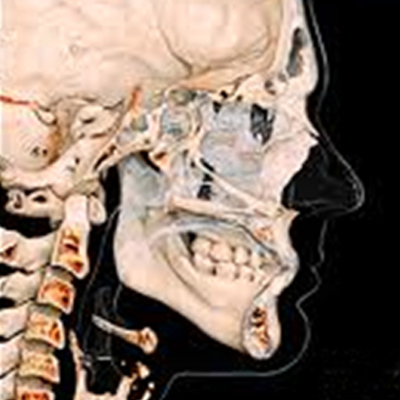

기존의 평면적이었던 X-ray나 파노라마 보다 더 정확하고 더 정밀한

3D CT를 이용하여 치아 뿌리의 상태, 위치, 이동 가능량, 잇몸뼈 등

치아와 잇몸 상태 뿐만 아니라 얼굴 골격까지 진단하여 오차없고 섬세한 치료계획을 수립합니다.